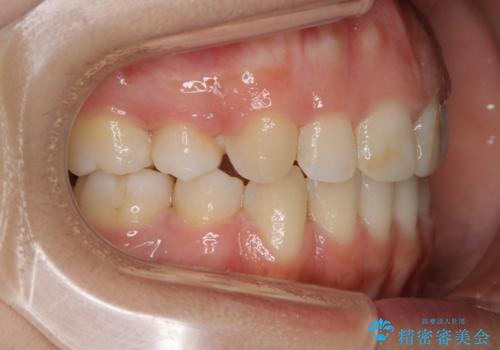

- 口元を下げたいという主訴でご来院されました。

ガタつきの度合いは軽度でしたが歯列の幅が狭く、その分前歯が上下とも前方に出てしまっていました。

しっかりと口元・顔貌まで変化を起こせるように上下左右の第一小臼歯を抜歯し、ワイヤー装置にて矯正を開始することとなりました。

抜歯矯正

叢生(ガタつき)が強い場合や上下もしくはどちらかの歯が前方に出ている場合、その問題を解決するためのスペース作りのため抜歯をすることがあります。

多くのケースは第一小臼歯を抜歯することで並べたい前歯のすぐ近くにスペースを作りガタつきや出っ歯を改善していきます。